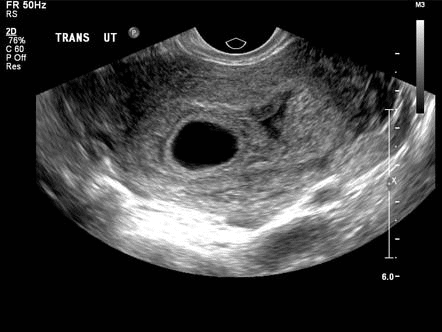

Saco gestacional

Ao realizar a avaliação da idade gestacional durante o pré-natal, é comum utilizar o tamanho do saco gestacional como uma medida inicial. No entanto, é importante ressaltar que essa medida não é recomendada para calcular a DPP com precisão.

Pontos-chave da avaliação da idade gestacional por meio do saco gestacional:

- O saco gestacional se torna claramente visível entre 4,5 e 5 semanas de gestação

- É um sinal duplo decidual que pode ser observado entre 5,5 e 6 semanas.

- Idade gestacional estimada (dias) = diâmetro médio do saco (MSD) em mm + 30

- O diâmetro médio do saco possui uma precisão de ±5 a 7 dias, porém não é suficientemente preciso para determinar com exatidão a idade gestacional, uma vez que gestações inviáveis também podem ser mensuráveis.